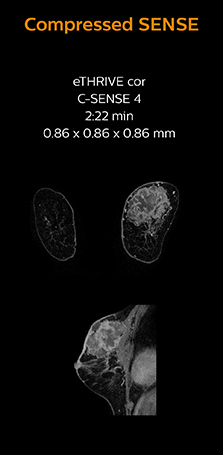

Identification of small breast lesions requires high resolution

Dr. Koyama says that he used to believe that high resolution MRI at 1.5T required long scan times, and SNR was low. “With Compressed SENSE, however, it is possible to acquire high quality images, even with higher Compressed SENSE factors, so in a quite short time.”

“In breast scanning, high resolution is important to help me identify very small mammary lesions, so, we need high spatial resolution in 2D T1- and T2-weighted images, as well as a short scan time. Compressed SENSE has allowed us to increase spatial resolution, which benefits our diagnostic confidence.”

Dr. Koyama says that a C-SENSE factor of 4.0 was chosen to increase their spatial resolution in 3D dynamic breast scanning. “In addition to a high temporal resolution, we also require high spatial resolution, which helps us to see details of the internal structure of the lesion and to see lesions separately from normal anatomic structures. We can also see if a lesion extends into adjacent organs and anatomic structures.”

3D MRI with Compressed SENSE of patient with breast cancer

This patient underwent MRI on Ingenia 1.5T with Compressed SENSE. Compressed SENSE was used to reduce the scan time in order to decrease the time that the patient may experience discomfort and pain, both of which may lead to patient motion. The 3D BreastVIEW and 3D high resolution mDIXON images – both mDIXON contrasts are acquired in the same exam – show high quality images even with the shorter scan time. The spatial resolution of the dynamic scan with Compressed SENSE is higher than in the previous protocol (not shown) which allows for better visualization of the lesion with respect to the muscles of the thoracic wall and better delineation of small structures.

For breast imaging, a fast, high resolution scan can be important for a female patient having to lie in an uncomfortable, face-down position in the scanner. Compressed SENSE also helps us to obtain higher1 quality images using 3D BreastVIEW and 3D high resolution mDIXON sequences in the same examination time as in our previous exam protocol.